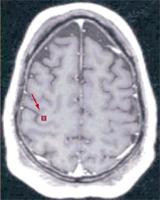

Cyberkinetics firması tarafından geliştirilen BCI sisteminin ana parçası "BrainGate", üzerinde 100 elektrot bulunan bir çip. 4x4m boyutlarındaki çip hastanın motor korteksine yerleştirilmiş.

Büyük beyin kabuğundaki bu bölge sağlıklı insanlarda beden hareketlerinin çalıştırılmasından sorumludur.

Ancak boyun omuriliğinden aşağısı felç olanlarda motor korteksin sinyalleri el ve kol kaslarına ulaşamıyor. Bu bağlantı ayrıca inme veya kas distrofisi gibi hastalıklarda da ortaya çıkabilmekte.

Motor korteks öte yandan çipin elektrotlarından çok daha fazla nörona sahip, yerleştirme bu nedenle sadece rastlantısal olarak mümkün olmakta. Bu yüzden yazılım programı ile, kaydedici 96 elektrotun yanında bulunan etkin beyin hücrelerinin elektriksel sinyalleri, değerlendirilebilir çalıştırma bilgisine dönüştürülmek zorundaydı ki bu da BCI sisteminin en önemli işlevi olmalıydı.

Amerikalı bilim adamları şimdi bu işlemi, maymun deneyleriyle elde ettikleri bilgilere bile bakmaksızın yerine getirebildiler. Üç yıldır felç olan hasta altı deneme aşamasında, bilgisayar faresini ne şekilde çalıştıracağını hayal etmeyi öğrenirken, elektrotlar bu düşünceye bağlı olarak "ateşlenen" nöronları kaydetmişler.